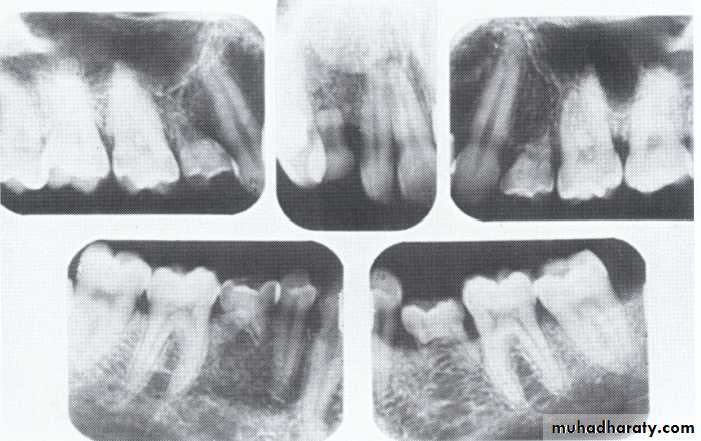

Type I (Radicular Type)

Dentin dysplasia, type I. panoramic & periapical films of the same case show the short and poorly developed roots, obliterated pulp chambers and root canals, and periapical inflammatory lesions.

Type II (Coronal Type)

Dentin dysplasia, type II. panoramic &periapical films of the same case show obliteration of the pulp chamber, reduction in the caliber of root canals, and pulp stones obscuring the flame-shaped pulp chambers.

Periapical inflammatory lesions are associated with some of the mandibular anterior teeth.